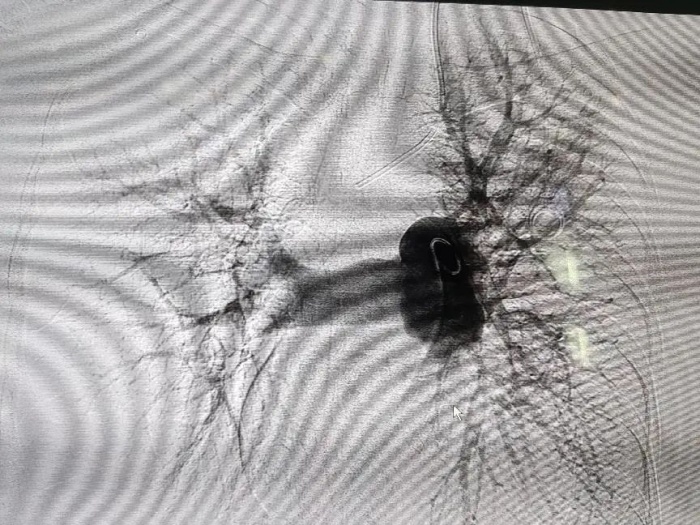

2024-07-31“10年前就是你們救了我……”百歲老人再次放下“心頭...

近日,南方醫(yī)科大學(xué)順德醫(yī)院肝膽胰脾外科團(tuán)隊(duì)為一名100歲膽石癥患者成功實(shí)施了微創(chuàng)取石術(shù)。十年前,當(dāng)時90歲的朱婆婆出現(xiàn)嚴(yán)重腹痛,在我院肝膽胰脾外科確診為膽總管結(jié)石并急性化膿性膽管炎、膽囊結(jié)石并急性化膿性膽囊炎。經(jīng)歷了ERCP、PTGD引流、...閱讀全文